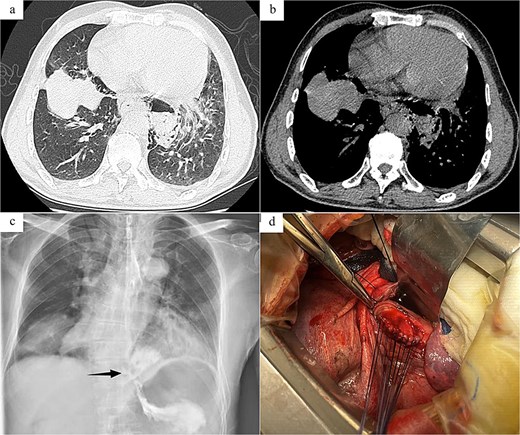

Case 2: The patient, a 54-year-old male, was admitted to Emergency Department due to “nausea, hematemesis accompanied by abdominal and thoracic pain for half a day.” On admission, imaging studies including chest and abdomen CT revealed periesophageal air around the lower segment of the esophagus, mediastinal emphysema, and multiple air in abdominal cavity, bilateral pleural effusion (Fig. 2a and b). Esophagus echoendoscopy showed contrast agent leakage at the distal aboral esophageal segment (Fig. 2c). Electrocardiogram showed no abnormalities. Blood routine test showed that white cell count 12.49 × 109/L, neutrophil count 11.19 × 109/L, neutrophil percentage 89.6%. In summary, the diagnosis was SRE. In emergent surgery under general anesthesia, laparoscopic repair of esophageal tear was performed. Intraoperative exploration revealed a long tear of about 3.0 cm in the posterior wall of the lower esophagus near the cardia (Fig. 2d), and the esophageal wall and mediastinal pleura around the tear were observed to have grayish-brown-like changes, and a long interspace about 5.0 cm was seen under the post-cardiac abdominal membrane, which was filled with gastric contents that had overflowed. The same surgical approach as Case 1 was employed. The surgical method was the same as Case 1. And a T-shaped tube was placed in the subphrenic space behind the cardia for drainage and drainage tubes were placed in the posterior mediastinum and the chest cavity, respectively. Postoperative anti-infection, gastrointestinal protection, and enteral nutrition therapy were given. Half a month after the operation, the patient was examined with upper digestive tract radiography and chest CT, which showed that there was no leakage or stenosis the anastomotic site of the esophagus. The patient was allowed to resume eating after fasting for 16 days and was discharged after recovery.

Radiology images and emergency surgery photos of spontaneous esophageal rupture (Case 2). (a and b) Chest and abdomen computed tomography revealed periesophageal air around the lower segment of the esophagus, mediastinal emphysema, multiple air in abdominal cavity, bilateral pleural effusion. (c) Esophagus echoendoscopy showed contrast agent leakage at the distal aboral esophageal segment (black arrow). (d) Emergency surgery revealed a long tear of about 3.0 cm in the posterior wall of the lower esophagus near the cardia.